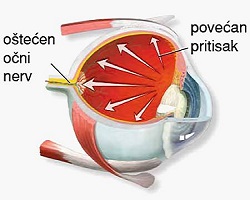

| Акутни глауком спада у групу најургентнијих стања у офталмологији, тако да захтева брзу дијагнозу и терапију. |

Процењује се да око 80 милиона људи широм света има глауком а 111,8 милиона људи има предиспозицију да добије глауком до 2040. године. У Србији је претпоставка да од ове болести болује око 100.000 људи јер не постоје прецизни подаци о оболелима јер глауком није болест која се обавезно пријављује. |